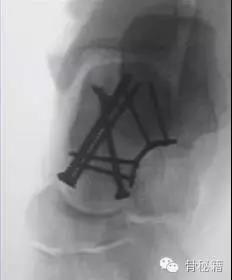

除去关节面的地方,就是我们最适合置放内固定的地方主要位于内侧和外侧

对于颈部的骨折,如果一侧钢板的位置不佳,则容易造成另外一侧的骨折裂开所以最好的固定是一侧用钢板固定,另外一侧可采用螺钉进行加压,避免另外一侧开口